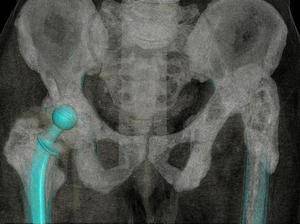

Значимость КТ основывается на возможности детального изучения структурных изменений костей при хроническом остеомиелите: выявлении периостита, зон деструкции, секвестрации кости.

Рис. 4. КТ таза. Мультипланарная реконструкция. Определяется костная деструкция в области крестцово-подвздошного сочленения.

Рис. 5. КТ таза. 3D-реконструкция. Остеомиелитическая деструкция лобковой кости.

Рис. 6. КТ пациентки с остеомиелитом подвздошной кости после эндопротезирования тазобедренного сустава.